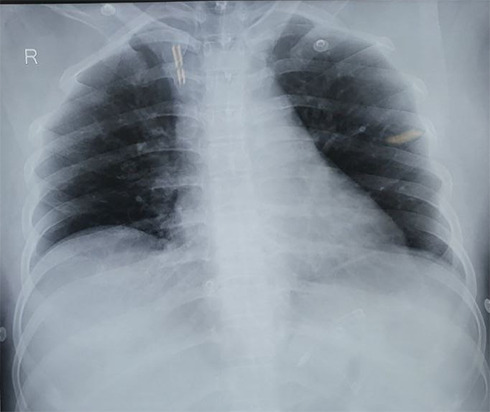

Cartap, a nereistoxin derivative from the marine annelid Lumbriconeresis heteropoda, is widely used as a pesticide, targeting pests like caterpillars. While the WHO classifies it as moderately hazardous, with a recommended daily intake of 0.05 mg/kg, human toxicity reports are limited. A 34-year-old female was admitted after consuming an unknown poison. She reported epigastric pain, burning sensations, sweating, vomiting, dyspnea, palpitations, and restlessness, compounded by alcohol intake. Initially treated for organophosphate poisoning, her cholinesterase level was 8.91. It was later confirmed she ingested 100 ml of 50% concentration cartap. Treatment included amiodarone for supraventricular tachycardia and intravenous N-acetylcysteine, magnesium sulfate, and midazolam for general tonic clonic seizure. Cartap, toxic through ingestion and skin contact, can cause symptoms such as vomiting, convulsions, and cardiac issues like supraventricular tachycardia. Supportive care is crucial, and awareness of its risks is necessary.